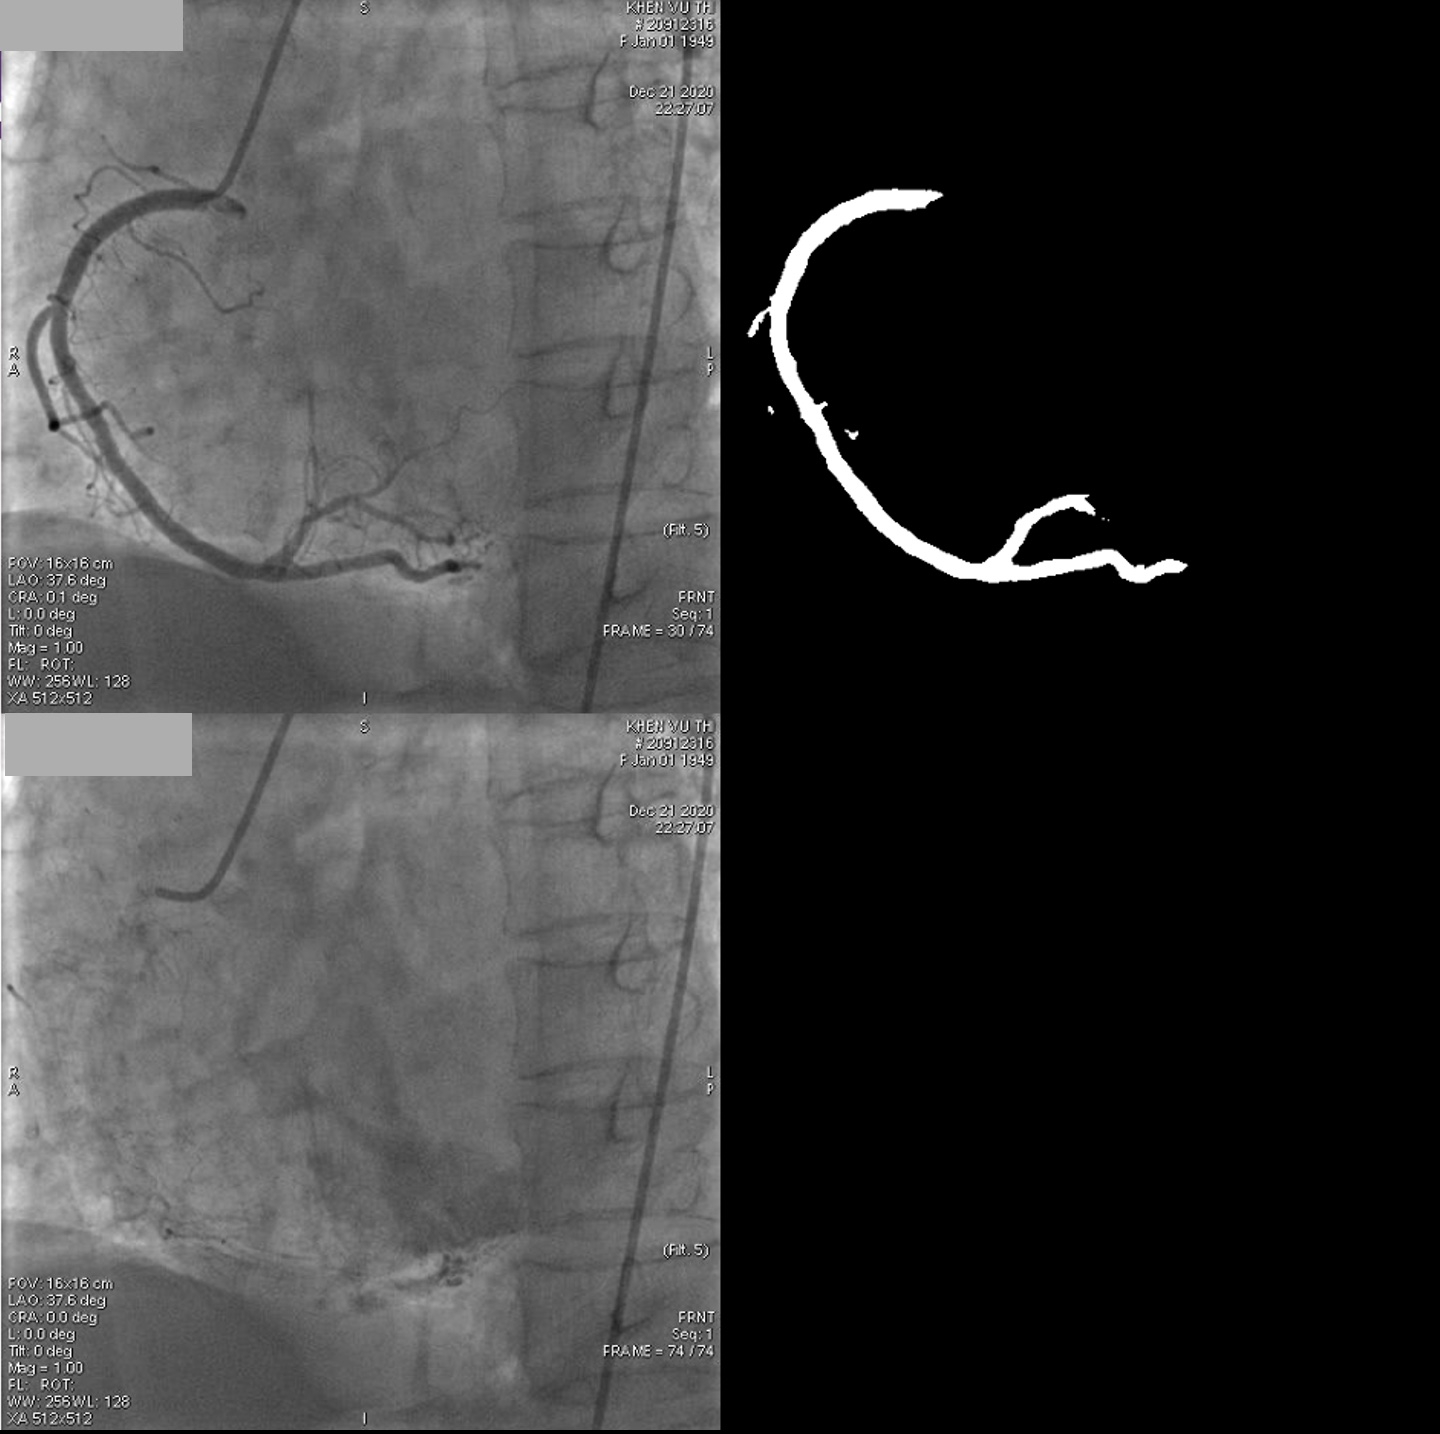

Methods: Patients with a single lesion admitted with diagnosed of unstable angina underwent the dynamic angiographic technique with IVUS support. First, the coronary artery was fully injected with contrast. After the injection stopped, the blood (white) began streaming in to replace the contrast (black). The flow characteristics and movements will be recorded through the disappearance of the contrast opacity with 15 frames/second. In aditionally, the arterial phase (AP) was calculated as the time from frames with full contrast to frames with washed-out contrast. Moreover, IVUS was performed for evaluate plaque features (eccentricity, calcification and vulnerable). At the same time, deep learning (DL) models were built based on independent datasets (225 angiogram videos). The DL program was constructed using a combination of U-Net and DenseNet-121. The segmentation model and a convolutional neural network were used to detect the starting frame, ending frame of AP.

Results: Fifty patients met inclusion criteria (72% males) with a mean age of 66.2 ± 9.5 years. IVUS analysis revealed that 84% (42 patients) had plaque eccentricity without (or minimal) calcification. Contrast stagnation was observed for a longer duration in eccentric coronary regions compared to non-eccentric plaque regions, as quantified by DL analysis of the arterial phase (24.5 +/- 1.6 frames vs 30.1+/- 1.4 frames, p < 0.05). After stenting, the stagnant flow was eliminated, and flow was restored to 25 ± 2.1 frames.